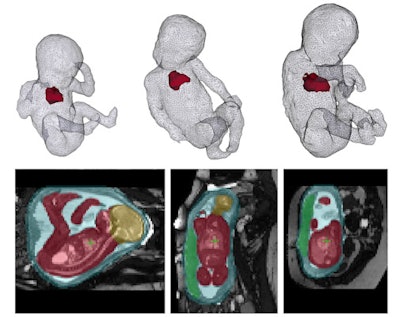

Along with Alena Uus, PhD, and Maria Deprez, PhD, I am also using AI to automatically localize the fetus in MRI images of a mother's uterus. The dataset is part of the iFind (intelligent Fetal Imaging Diagnosis) project, led by clinicians from KCL; St Thomas' Hospital; Imperial College; the University of Florence in Italy; the Hospital for Sick Children in Toronto, Canada; and Philips Healthcare. In this work, not only do we try to detect the fetus in the images but also its different organs, which will ultimately help improve the information available for clinicians to perform their diagnosis.